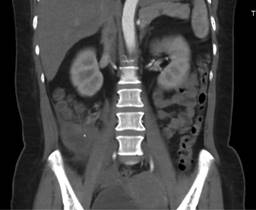

Tomografía simple y contrastada abdominopélvica 03/11/22: colección sub y retrocecal de 50 cm3 con proceso inflamatorio periférico, lo cual sugiere proceso apendicular complicado (Figuras 1 y 2).

Figura 1: Tomografía simple y contrastada de abdomen, corte sagital. En cuadrante inferior derecho con presencia de cambios inflamatorios de la grasa pericecal.

Figura 2: Tomografía simple y contrastada de abdomen, corte coronal. En fosa iliaca derecha se observa imagen circunscrita de densidad cálcica.